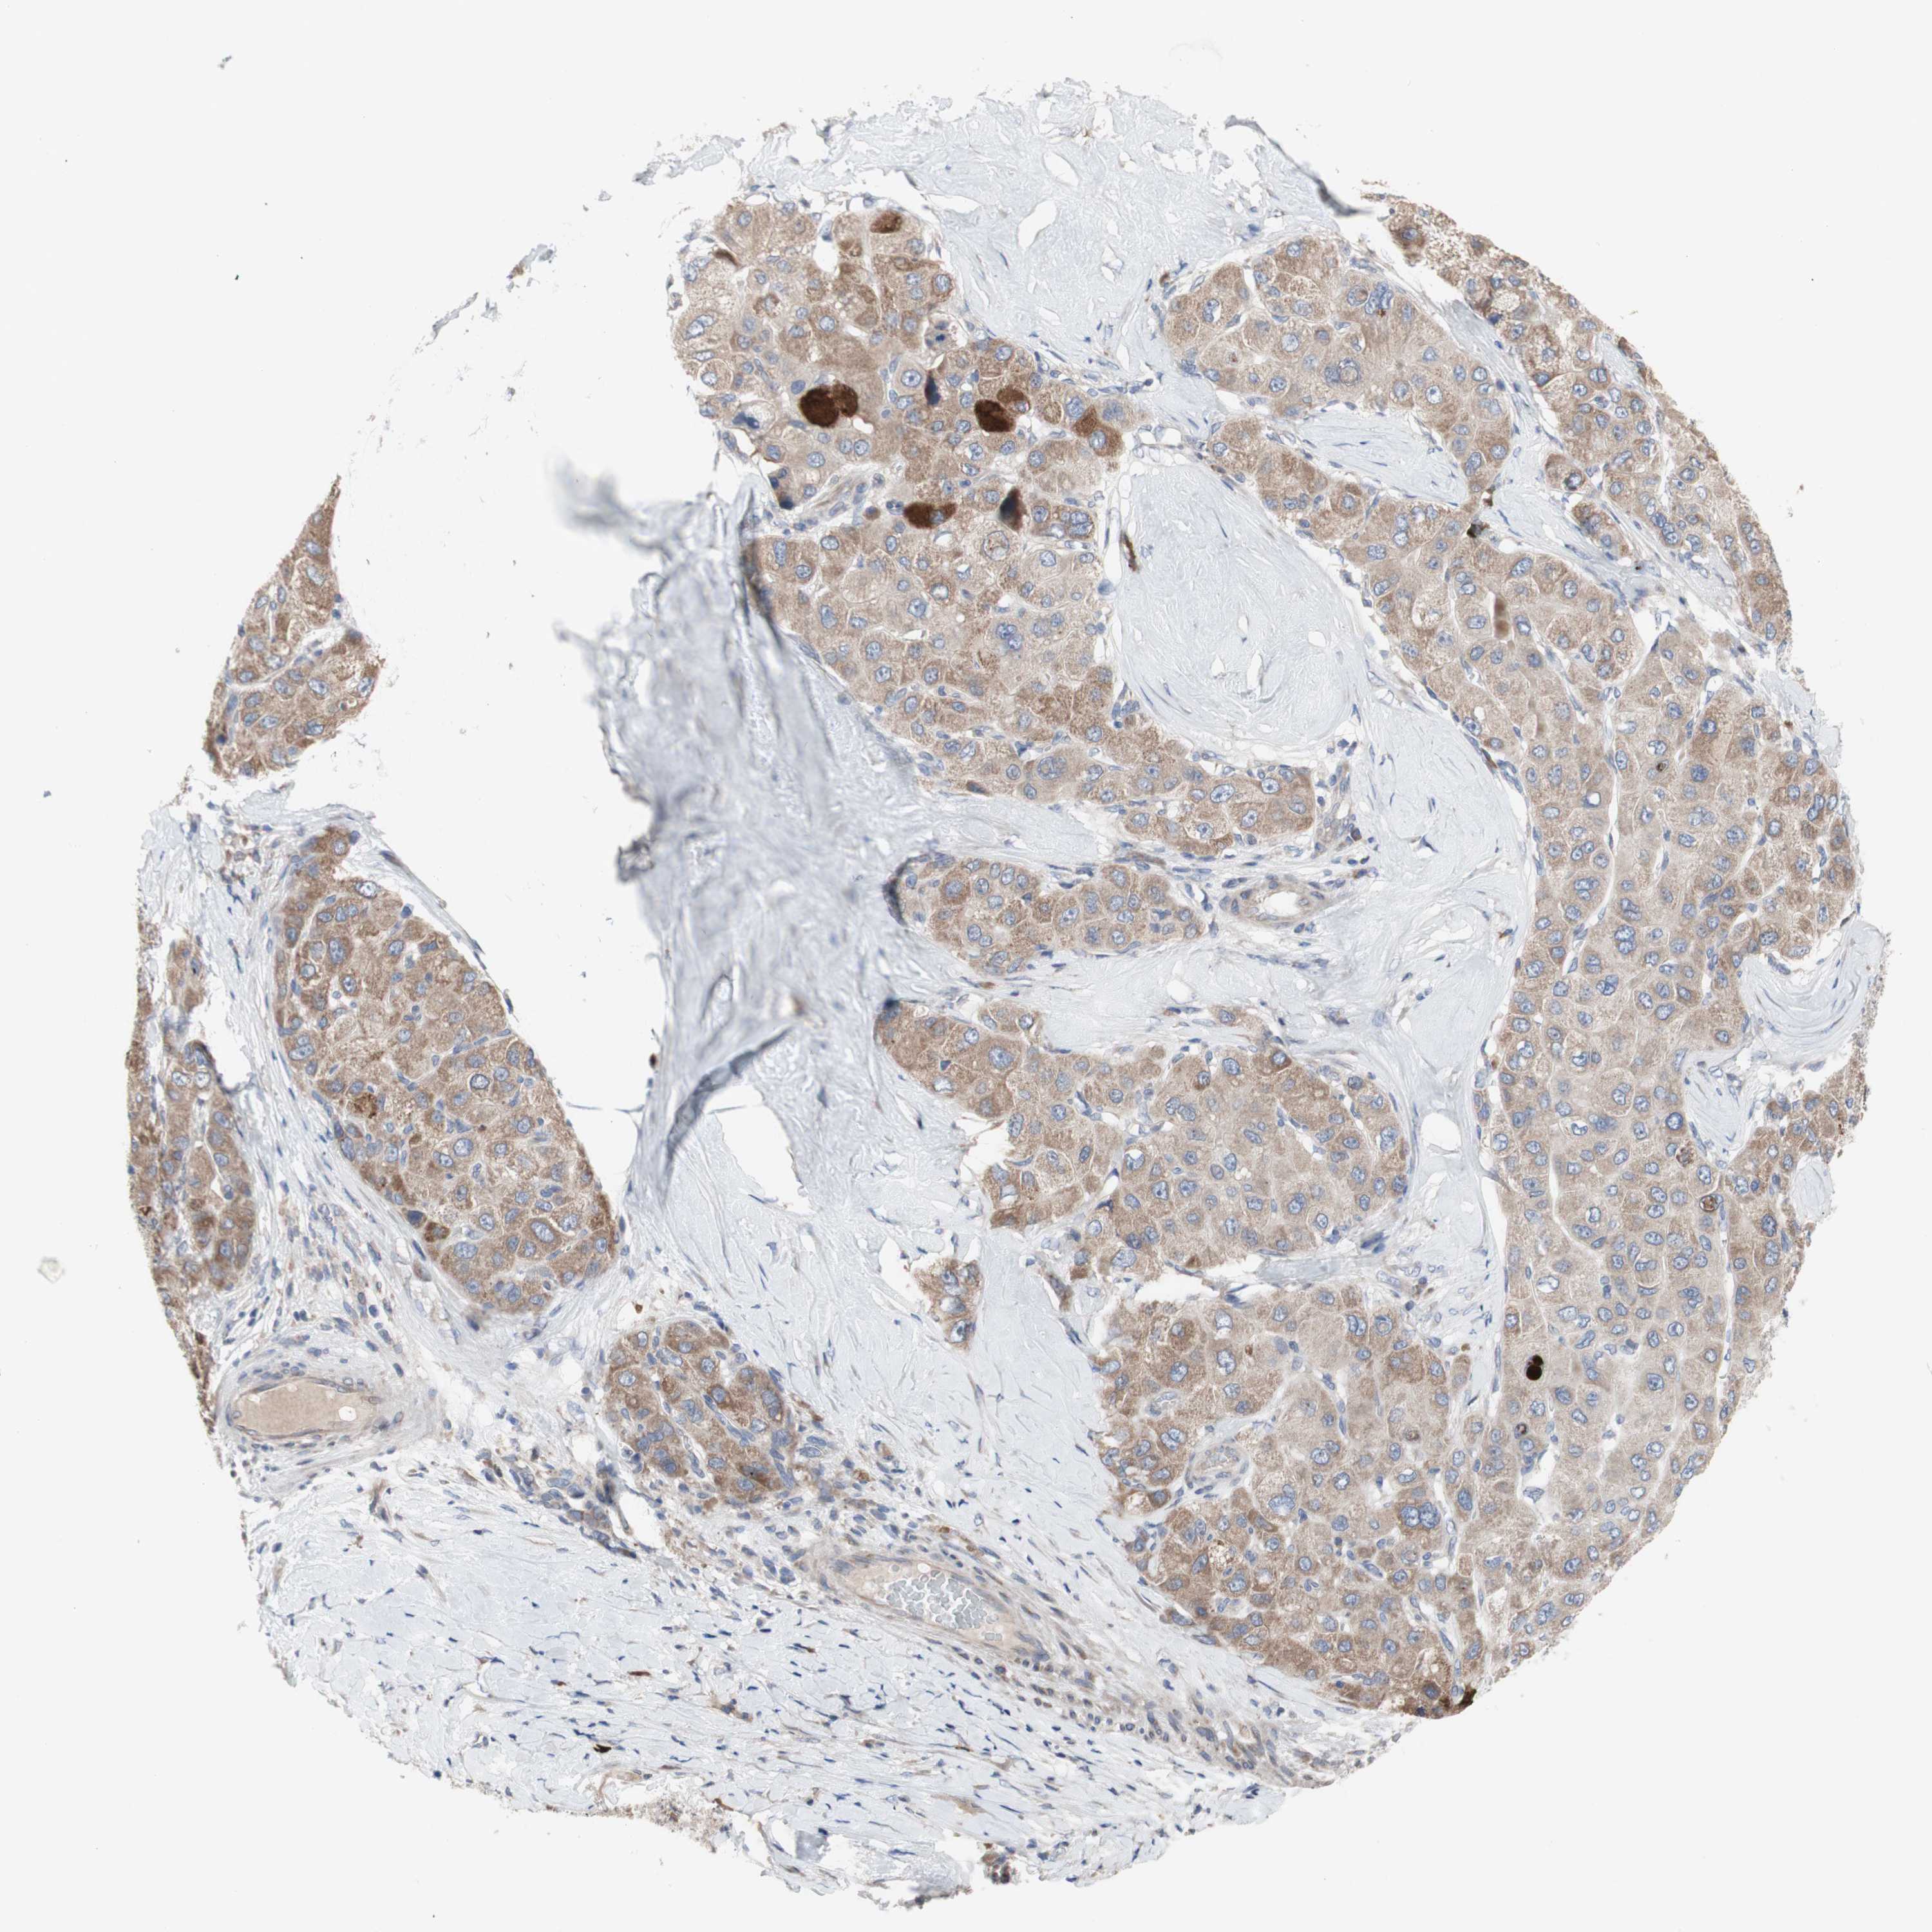

LIVER CANCER - Protein expressioni

A mouse-over function shows sample information and annotation data. Click on an image to view it in a full screen mode. Samples can be filtered based on level of antibody staining by selecting one or several of the following categories: high, medium, low and not detected. The assay and annotation is described here.

Note that samples used for immunohistochemistry by the Human Protein Atlas do not correspond to samples in the TCGA dataset.

Antibody stainingi

Antibody staining in the annotated cell types in the current human tissue is reported as not detected, low, medium, or high, based on conventional immunohistochemistry profiling in selected tissues. This score is based on the combination of the staining intensity and fraction of stained cells.

Each image is clickable and will lead to virtual microscopy that enables deeper exploration of all samples and also displays staining intensity scores, fraction scores and subcellular localization as well as patient and tissue information for each sample.

Antibody HPA009295

Staining

High

Medium

Low

Not detected

Intensity

Strong

Moderate

Weak

Negative

Quantity

>75%

75%-25%

<25%

None

Location

Nuclear

Cytoplasmic/membranous

Cytoplasmic/membranous,nuclear

Cholangiocarcinoma

Carcinoma, Hepatocellular, NOS